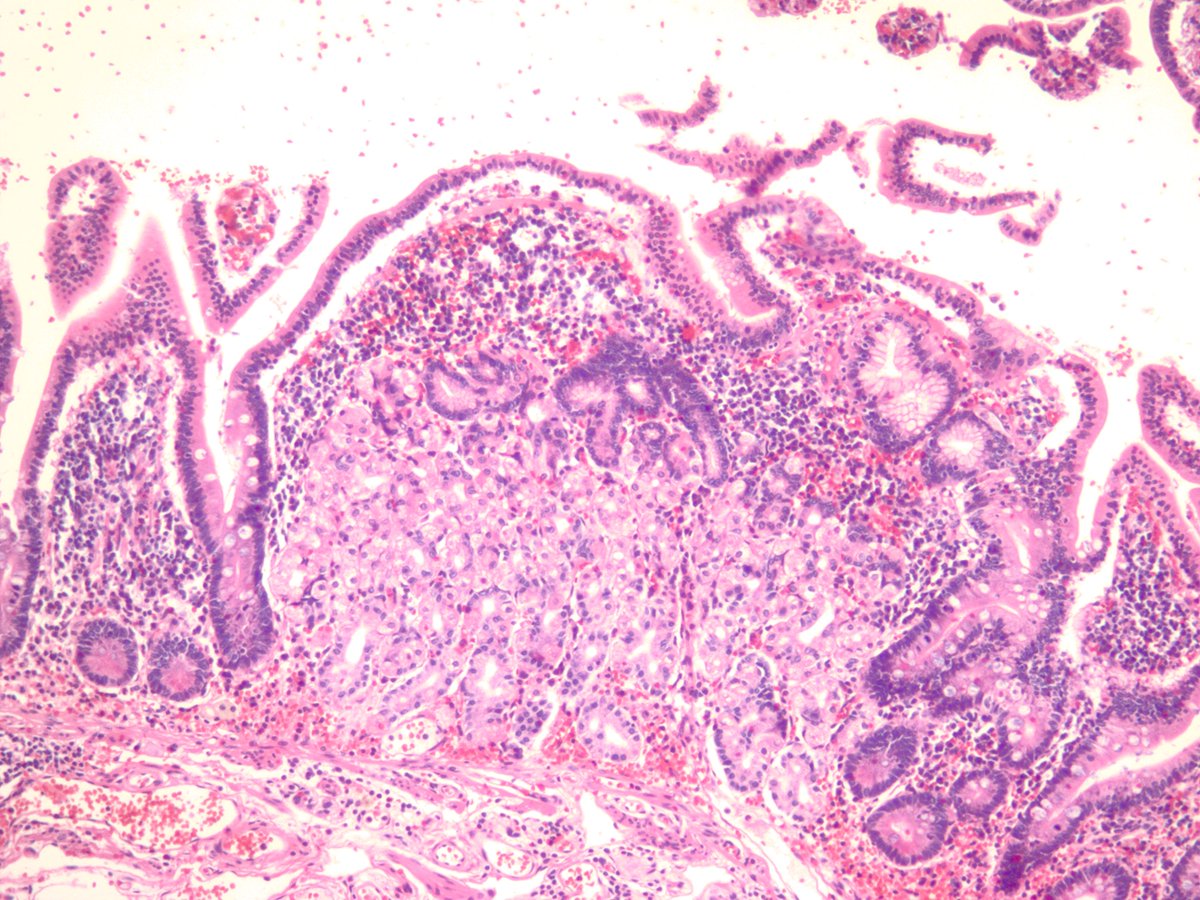

Meckel's diverticulum with pancreatic and gastric heterotopia. #GIpath #pathology

jake_bledsoe's tweet image. Meckel's diverticulum with pancreatic and gastric heterotopia. #GIpath #pathology